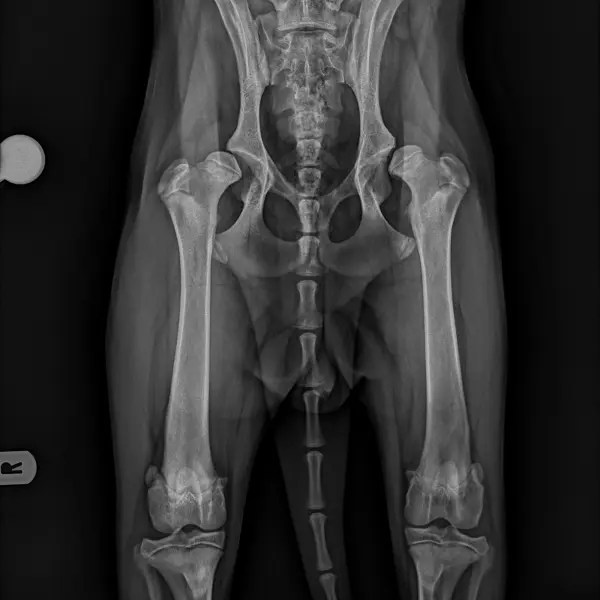

El diagnóstico de la displasia de cadera generalmente se alcanza a través de un completo examen ortopédico y con la realización de un estudio radiológico de las caderas bajo sedación o anestesia general. En este último los hallazgos pueden ser variables, desde incongruencia articular, hasta presencia de signos de degeneración articular (artrosis) como puede ser la deformidad coxofemoral y la aparición de osteofitosis (depósitos anormales de hueso) en la articulación.